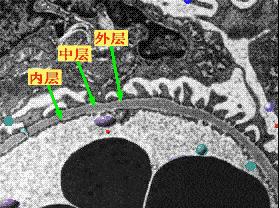

血液中90%是水,另外10%是由白细胞、蛋白质和身体里其他的代谢物质构成。血液流到肾脏时,需要依次经过肾小球、微管道、小管道、粗管道。在这个过程中,它们会将身体所需的物质挑出来,留下。